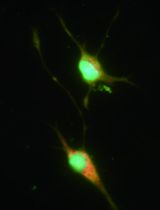

Chronic low-degree tissue inflammation, accompanied by enhanced immune cell infiltration, is a hallmark of obesity in both rodent and human and is a major causal factor for the pathogenesis of insulin resistance through promoting the inflammation status and interrupting the insulin signalling (Romeo et al., 2012; Johnson and Olefsky, 2013; Saltiel and Olefsky, 2017). The infiltrated immune cells such as pro-inflammatory macrophages and B cells play critical roles in modulating obesity-associated adipose tissue inflammation and insulin resistance (Weisberg et al., 2003; Winer et al., 2011). Chronic nutrient excess drives adipose tissue macrophages (ATMs) to undergo a unique phenotypic switch from anti-inflammatory M2-like activation in lean adipose tissue to a more pro-inflammatory M1-like activation state in obese tissues (Lumeng et al., 2007; Nguyen et al., 2007; Lumeng et al., 2008). Pro-inflammatory M1-like ATMs contribute to the development of tissue inflammation and systemic insulin resistance in obesity. Our recent study also demonstrates that leukotriene B4 (LTB4)-induced recruitment and activation of adipose tissue B2 (ATB2) cells can cause obesity-induced insulin resistance (Ying et al., 2017). In this protocol, we provide a step-by-step procedure to isolate stromal vascular cells from adipose tissue and characterize various immune cells in adipose tissues.